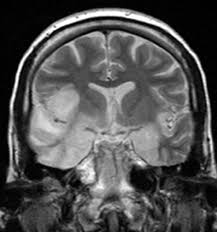

Pcr was repeated on the biopsy specimen and was positive for hsv. Limbic encephalitis, mca ischaemia, tumours, effects of seizures) hyperintense t2 signal in the medial temporal lobes, inferior frontal lobes and insula basal ganglia are usually spared Axial t2 prominent swelling, increase t2 signal involving the left temporal lobe and insular cortex. Multilocularis, and describes a spectrum of disease involving the spinal cord, the spine, or both. Mri is the diagnostic modality of choice abnormal in 90%; A brain biopsy was performed and the histology was consistent with encephalitis. Mri demonstrates extensive edema in the right temporal lobe with areas of intrinsic high t1 signal, in keeping with hemorrhage. For a general discussion, and for links to other system specific manifestations, please refer to the article on hydatid disease.

The basal ganglia are usually spared. Mri is the diagnostic modality of choice abnormal in 90%; Hsv encephalitis | radiology case | radiopaedia.org. Axial t2 prominent swelling, increase t2 signal involving the left temporal lobe and insular cortex. For a general discussion, and for links to other system specific manifestations, please refer to the article on hydatid disease. Herpes simplex (hsv) encephalitis is the most common cause of fatal sporadic fulminant necrotizing viral encephalitis and has characteristic imaging findings. Herpes simplex virus (hsv) is a human herpesvirus that causes hsv encephalitis (hse), which is the commonest fatal sporadic encephalitis in humans. Hse may result from primary infection or reactivation from latency, and it frequently involves frontal or temporal lobes, as well as the brain stem. The differential diagnoses include limbic encephalitis (paraneoplastic), gliomatosis cerebri, and status epilepticus. A brain biopsy was performed and the histology was consistent with encephalitis. For a general discussion, and for links to other system specific manifestations, please refer to the article on hydatid disease. Cerebral malaria is a rare intracranial complication of a malarial infection. Bilateral temporal lobe t2 hyperintensity refers to hyperintense signal involving the temporal lobes on t2 weighted and flair imaging.

The differential diagnoses include limbic encephalitis (paraneoplastic), gliomatosis cerebri, and status epilepticus. Ventriculitides) refers to inflammation, usually due to infection, of the ependymal lining of the cerebral ventricles. For a general discussion, and for links to other system specific manifestations, please refer to the article on coccidioidomycosis. Herpes simplex (hsv) encephalitis is the most common cause of fatal sporadic fulminant necrotising viral encephalitis and has characteristic imaging findings. Bilateral temporal lobe t2 hyperintensity refers to hyperintense signal involving the temporal lobes on t2 weighted and flair imaging. For a general discussion, and for links to other system specific manifestations, please refer to the article on hydatid disease. Given the history of fever and seizures coupled with the mri findings of bilateral mesial temporal lobe changes, herpes encephalitis requires clinical consideration. It is most often due to meningitis. Multilocularis.the larval stage is the cause of hydatid disease in humans 1. Spinal hydatid disease is an uncommon manifestation of hydatid disease, caused by the larval stage of echinococcus granulosus, or less commonly e. Terminology cerebritis is essentially the same as encephalitis except that it is used to denote brain par. It is a common finding on brain mri and a wide range of differentials should be considered 1. It is usually bilateral but asymmetrical.

The changes spare the basal ganglia, a feature which is helpful in distinguishing an mca infarct with hemorrhagic transformation from herpes simplex encephalitis, the diagnosis in this case. Hse may result from primary infection or reactivation from latency, and it frequently involves frontal or temporal lobes, as well as the brain stem. Herpes simplex (hsv) encephalitis is the most common cause of fatal sporadic fulminant necrotizing viral encephalitis and has characteristic imaging findings. It is usually bilateral but asymmetrical. The differential diagnoses include limbic encephalitis (paraneoplastic), gliomatosis cerebri, and status epilepticus. Two subtypes are recognized which differ in demographics, virus, and pattern of involvement. Given the history of fever and seizures coupled with the mri findings of bilateral mesial temporal lobe changes, herpes encephalitis requires clinical consideration. Spinal hydatid disease is an uncommon manifestation of hydatid disease, caused by the larval stage of echinococcus granulosus, or less commonly e. Multilocularis.the larval stage is the cause of hydatid disease in humans 1. The differential diagnoses include limbic encephalitis (paraneoplastic), gliomatosis cerebri, and status epilepticus. Herpes simplex encephalitis (hse) is the most common form of viral sporadic encephalitis and, when left untreated, has a mortality rate of 70% (3, 22). This patient went on to have hsv encephalitis proven on csf pcr. Bilateral temporal lobe t2 hyperintensity refers to hyperintense signal involving the temporal lobes on t2 weighted and flair imaging.